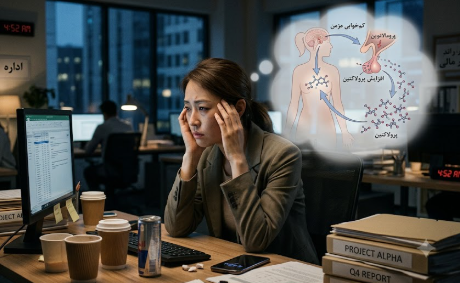

مکانیسم ارتباط D‑dimer مزمن بالا و سکته در APS

در APS نهفته، سیستم ایمنی آنتیبادیهایی تولید میکند که به فسفولیپیدهای سطح سلولهای اندوتلیال و پلاکتها متصل میشوند.

این پیوند باعث:

- فعال شدن مداوم پلاکتها و ترشح فاکتورهای لختگی

- آسیب اندوتلیوم و کاهش عملکرد ضدانعقادی طبیعی

- تشکیل میکروترومبوز در مویرگهای مغزی و کرونری

میشود.

در چنین شرایطی، سطح D‑dimer به شکل مزمن بالا میماند، حتی در غیاب نشانههای ظاهری ترومبوز. این افزایش مداوم، در واقع سیگنال هشدار بدن از وجود فعالیت لختهسازی زیرسطحی است.